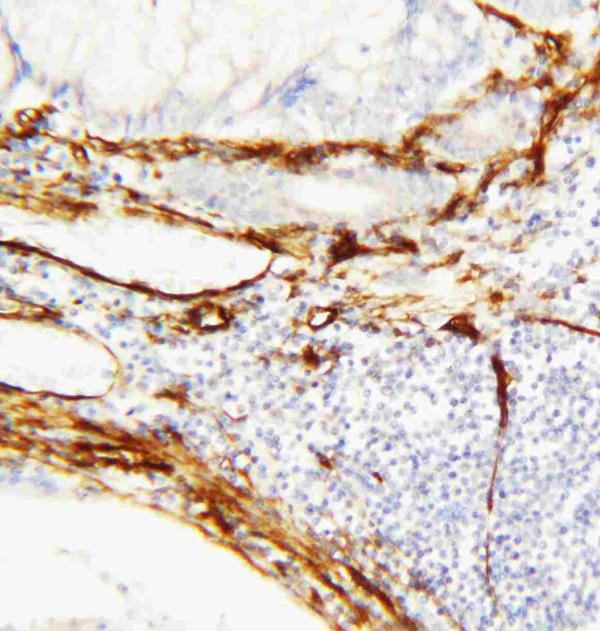

(Anti-Caveolin-1 antibody, AAA45172, IHC(P)IHC(P): Human Mammary Cancer Tissue)

IHC (Immunohiostchemistry)